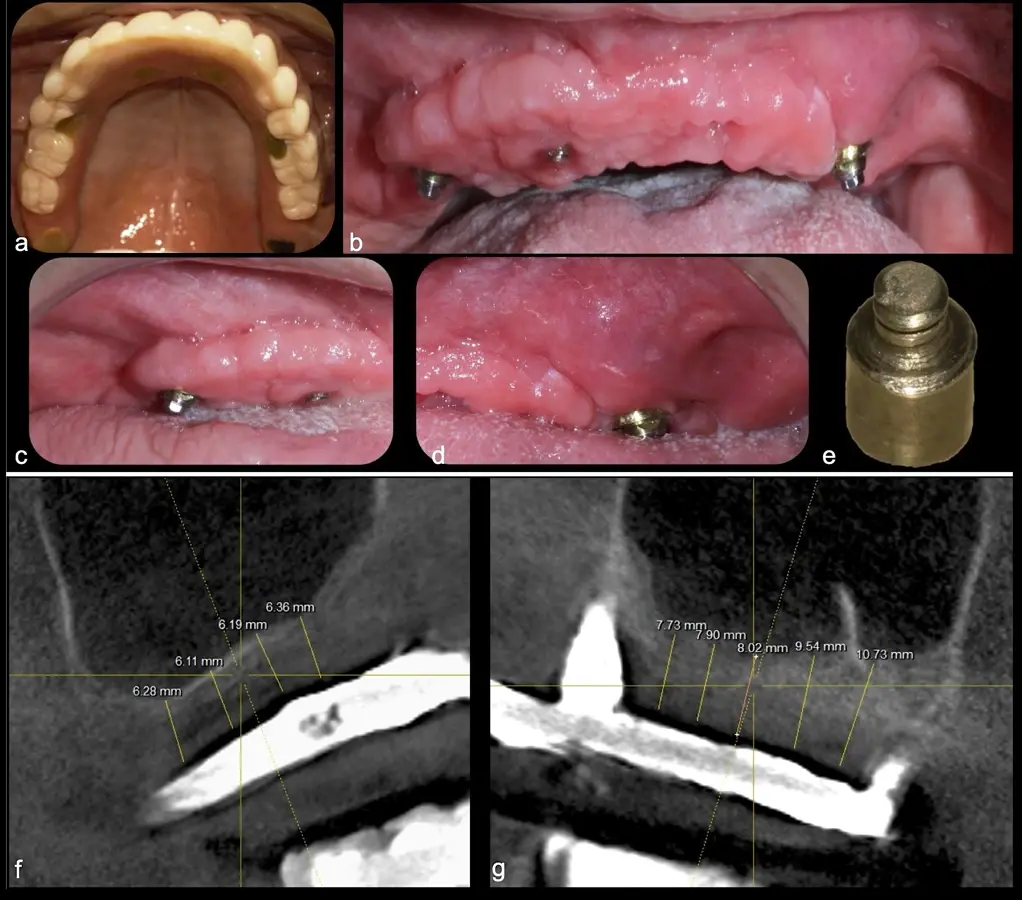

Aplicaciones clínicas: Levantamiento de piso de seno maxilar

La técnica se inicia con la colocación de anestesia infiltrativa, posteriormente se realiza una incisión crestal o paracrestal con posibles liberantes verticales que deben de estar alejadas por lo menos 5 mm de los límites de la futura ventana y sobrepasar la línea mucogingival. Se realiza una elevación de colgajo, se inicia la antrostomía y antroplastía. Para ello, se emplea el inserto redondo diamantado de corte al momento de delimitar los bordes de la ventana de acceso. Luego se cambia al inserto aserrado liso de calibre fino con superficie diamantada, para profundizar y eliminar el hueso en el contorno de la ventana. Una vez que se traslucen los tejidos, se puede optar por el retiro de la tapa ósea o el levantamiento de ésta junto con la membrana.

Se inicia la elevación de la membrana de Schneider con el inserto redondeado no cortante en forma de disco, empleando movimientos suaves. El levantamiento puede complementarse con elevadores convencionales, siguiendo la dirección mesiodistal. La fase de desprendimiento inicia con el piso y sigue hacia la pared mesial para terminar, y de ser necesario, hacia la pared posterior. Existen diversos insertos con angulaciones y longitudes para mayor accesibilidad16 (Figura 1).

El tipo de inserto a ser utilizado dependerá del espesor de la pared ósea. Si la pared es menor a 0.5 mm, es mejor utilizar insertos de desgaste para prevenir la ruptura de la membrana de Schneider; si el espesor es mayor a 0.5 mm, se puede utilizar insertos de corte de espesor medio (Figura 3).

El clínico puede retirar la tabla ósea o introducirla como “tienda de campaña” dentro del seno maxilar. En cualquiera de las alternativas, es importante evaluar la presencia de tabiques óseos y de la arteria postero alveolar superior.